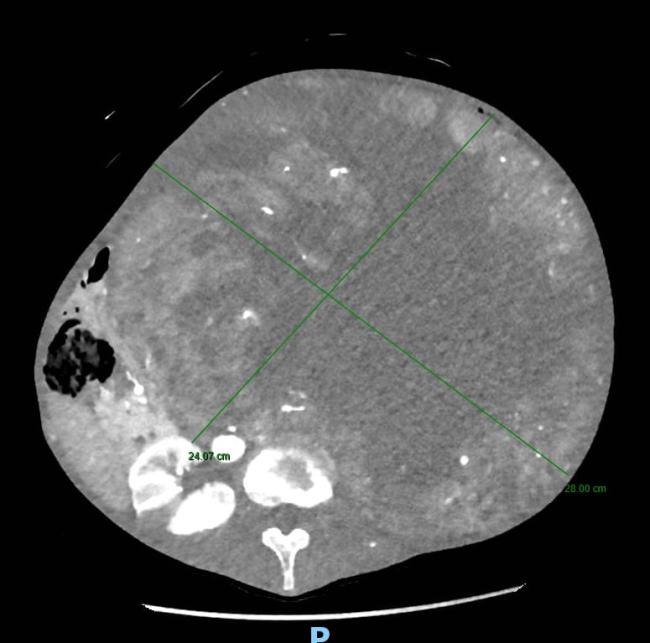

Tuttavia, alla visita clinica era da subito apparso evidente che il sintomo stipsi era secondario alla presenza di una voluminosa massa addominale di dimensioni spropositate che i successivi accertamenti diagnostici rivelavano essere a partenza dal rene sinistro. Tale massa – paragonabile a un grosso cocomero – occupava ormai l’intera cavità addominale, comprimendo oltre all’intestino tenue ed al colon, organi importanti quali il fegato, la milza, lo stomaco, il pancreas ed il duodeno e compromettendo la circolazione sanguigna di tali strutture.